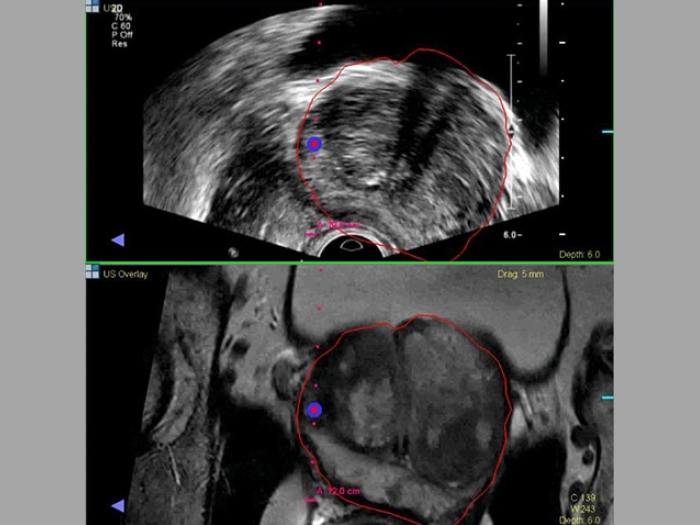

Prostate Cancer Biopsy

Health Lab

How Technology Is Making Prostate Cancer Biopsies More Precise

Learn more about how Michigan Medicine specialists are combining new techniques to improve prostate cancer diagnosis.